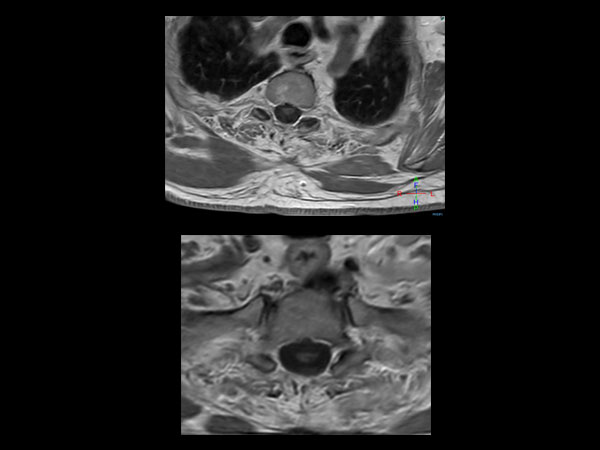

51 year-old man with poor general health and neurological disturbances. Histological examination of the surgical specimen led to the diagnosis of lipomatous ependynoma. Post surgery MRI (resected ependynoma) performed with dS HeadNeck coil with coverage till T4.